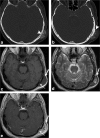

Calvarial lesions are often asymptomatic and are usually discovered incidentally during computed tomography or magnetic resonance imaging of the brain. Calvarial lesions can be benign or malignant. Although the majority of skull lesions are benign, it is important to be familiar with their imaging characteristics and to recognise those with malignant features where more aggressive management is needed. Clinical information such as the age of the patient, as well as the patient's history is fundamental in making the correct diagnosis. In this article, we will review the imaging features of both common and uncommon calvarial lesions, as well as mimics of these lesions found in clinical practice. TEACHING POINTS: • Skull lesions are usually discovered incidentally; they can be benign or malignant. • Metastases are the most frequent cause of skull lesions. • Metastatic lesions are most commonly due to breast cancer in adults and neuroblastoma in children. • Multiple myeloma presents as the classic "punched out" lytic lesions on radiographs. • Eosinophilic granuloma is an osteolytic lesion with bevelled edges.